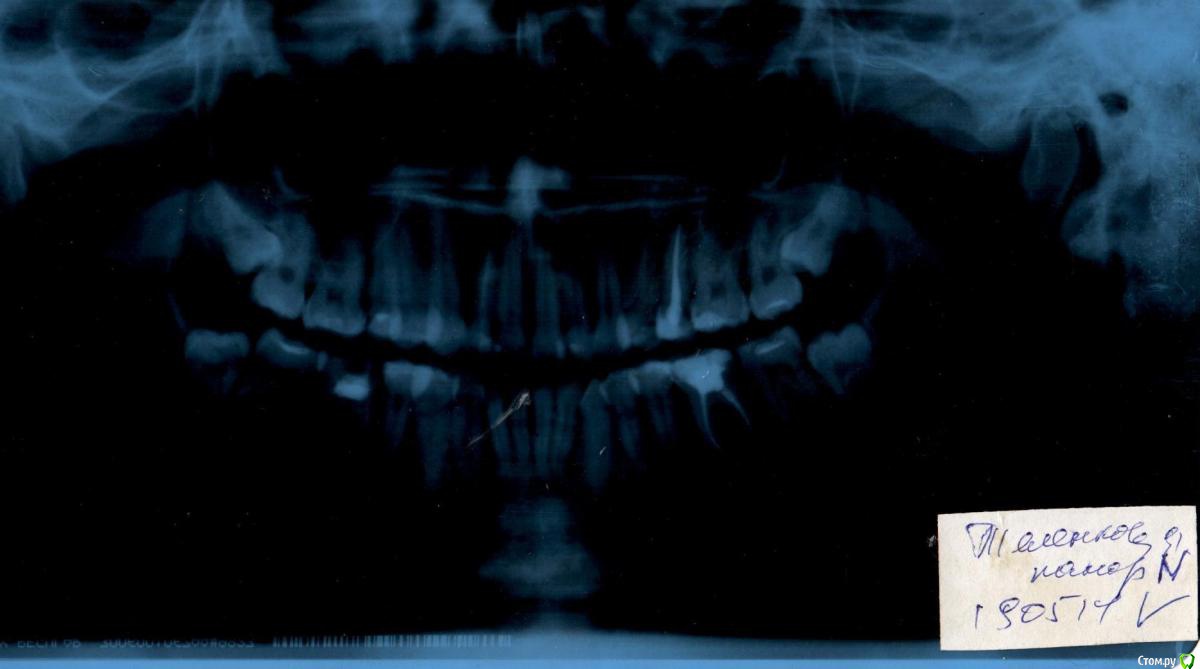

holden777 Опубликовано 11 июня, 2015 Поделиться Опубликовано 11 июня, 2015 (изменено) Добрый день всем! Очень надеюсь на советы профессионалов и их помощь!В 2012 году у меня началось оседание десны. Первые 1,5 года бегала по врачам, сдавала анализы, терапевты твердили, что это авитоминоз и сниженный иммунитет. В течении этого времени 3ка снизу очень искривилась. Слава богу,попался толковый специалист и сказал мне обратиться к ортодонту. Тут все и началось. Была у нескольких специалистов, никак не могу решиться, что мне лучше всего сделать. 1 - один специалист (лучший ортодонт в городе) советует удалить верхние зубы мудрости, снизу удалить 6-ки, они у меня мертвые. Далее поставить две системы самолигирующих брекетов. 2 - второй специалист советует снизу удалить 6-ки, а вверху - или зубы мудрости или 4ки. Далее - носить каппу сначала. Если не поможет, то брекеты.У меня несколько вопросов.1. Если удалить зубы мудрости и верхние и нижние, прекратится ли оседание десны и искривление зубов?2. Обязательно ли ставить брекеты? В эстетическом смысле меня устраивает, как выглядят зубы. Но специалист 1 говорит, что зубы надо обязательно растянуть,чтобы снять с них нагрузку, т.к. зубы мудрости их толкают в кучу.3. Вылезут ли зубы мудрости снизу, если удалить 6ки? Ведь там останется большой промежуток. Какова вероятность того, что промежуток закроется?4. При использовании брекетов не станет ли десна еще больше оседать? Не появятся ли промежутки между зубами?Очень прошу вашей помощи. За постановку брекетов и лечение нужно отдать немалые деньги. Я хочу быть уверена в том, что это действительно необходимо и без этого лечения нельзя обойтись. Просто хочу знать, достаточно ли будет просто удалить лишние зубы, которые способствуют искривлению других зубов и оседанию десны?Буду ждать ваших откликов, ребята!Если нужно сделать дополнительные фотографии, я сделаю. Снимок панорамный сделан год назад. В конце июня мне исполнится 26 лет. Изменено 11 июня, 2015 пользователем holden777 Ссылка на комментарий

holden777 Опубликовано 11 июня, 2015 Автор Поделиться Опубликовано 11 июня, 2015 Фотографии: Ссылка на комментарий